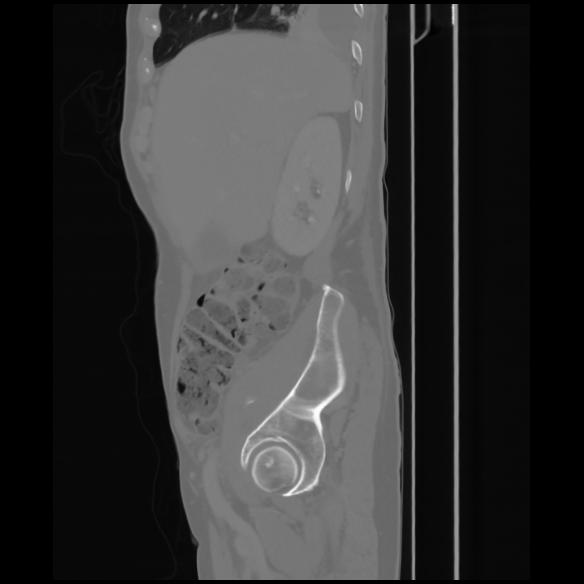

7 CUERPO,CE,Sagittal,3.000,CUERPO,Sagittal,